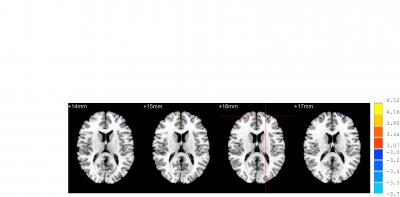

Both acupuncture at Waiguan (SJ5) and sham acupuncture can activate/deactivate several brain regions in patients with ischemic stroke, but there are some difference in Brodmann areas 4, 6, 8, Brodmann areas 7, 39, 40, Brodmann areas 18, 19, 22 and Brodmann areas 13, 24, 32, 28. Most studies addressing the specificity of meridians and acupuncture points have focused mainly on the different neural effects of acupuncture at different points in healthy individuals. Dr. Ji Qi and co-workers from School of Traditional Chinese Medicine, Southern Medical University in China examined the effects of acupuncture on brain function in a pathological context, and compared the effects between Waiguan and sham points in 16 patients with ischemic stroke. Compared with sham acupuncture, acupuncture at Waiguan in stroke patients inhibited Brodmann area 5 on the healthy side. These findings, published in the Neural Regeneration Research (Vol. 9, No. 3, 2014), indicated that the altered specificity of sensation-associated cortex (Brodmann area 5) is possibly associated with a central mechanism of acupuncture at Waiguan for stroke patients.